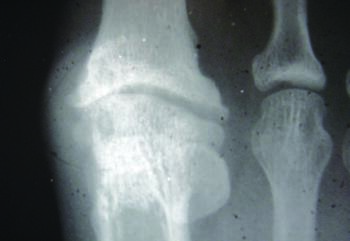

Stage 1. In this stage of the classification system only 30 to 40 degrees of dorsiflexion is available for the hallux to dorsiflex passively.17 There will be some dorsal spurring on radiograph, with minimal narrowing of the joint space. The patient will describe intermittent mild pain, typically at the end stage of first MPJ range of motion. These clinical and radiographic findings are consistent with early hallux limitus.

Stage 2. In stage 2, there is more dramatic loss in dorsiflexion at the first MPJ with only 10 to 30 degrees of dorsiflexion remaining, which can make ambulation difficult as well as painful.17 Radiographically, a more extensive dorsal osteophyte will be seen than in stage 1, with further decrease in the joint space. This stage now represents a structural hallux limitus.

Radiographic findings may be subtle or negative in the early phases of the condition.18 As the condition progresses, radiographic findings may reveal joint narrowing, thinning of articular surfaces, osteophytic changes of the base of the proximal phalanx, spurring of the metatarsal head, and possible fracture fragments/loose bodies. If previous injury to the sesamoids occurred, there may be degenerative changes there as well.18